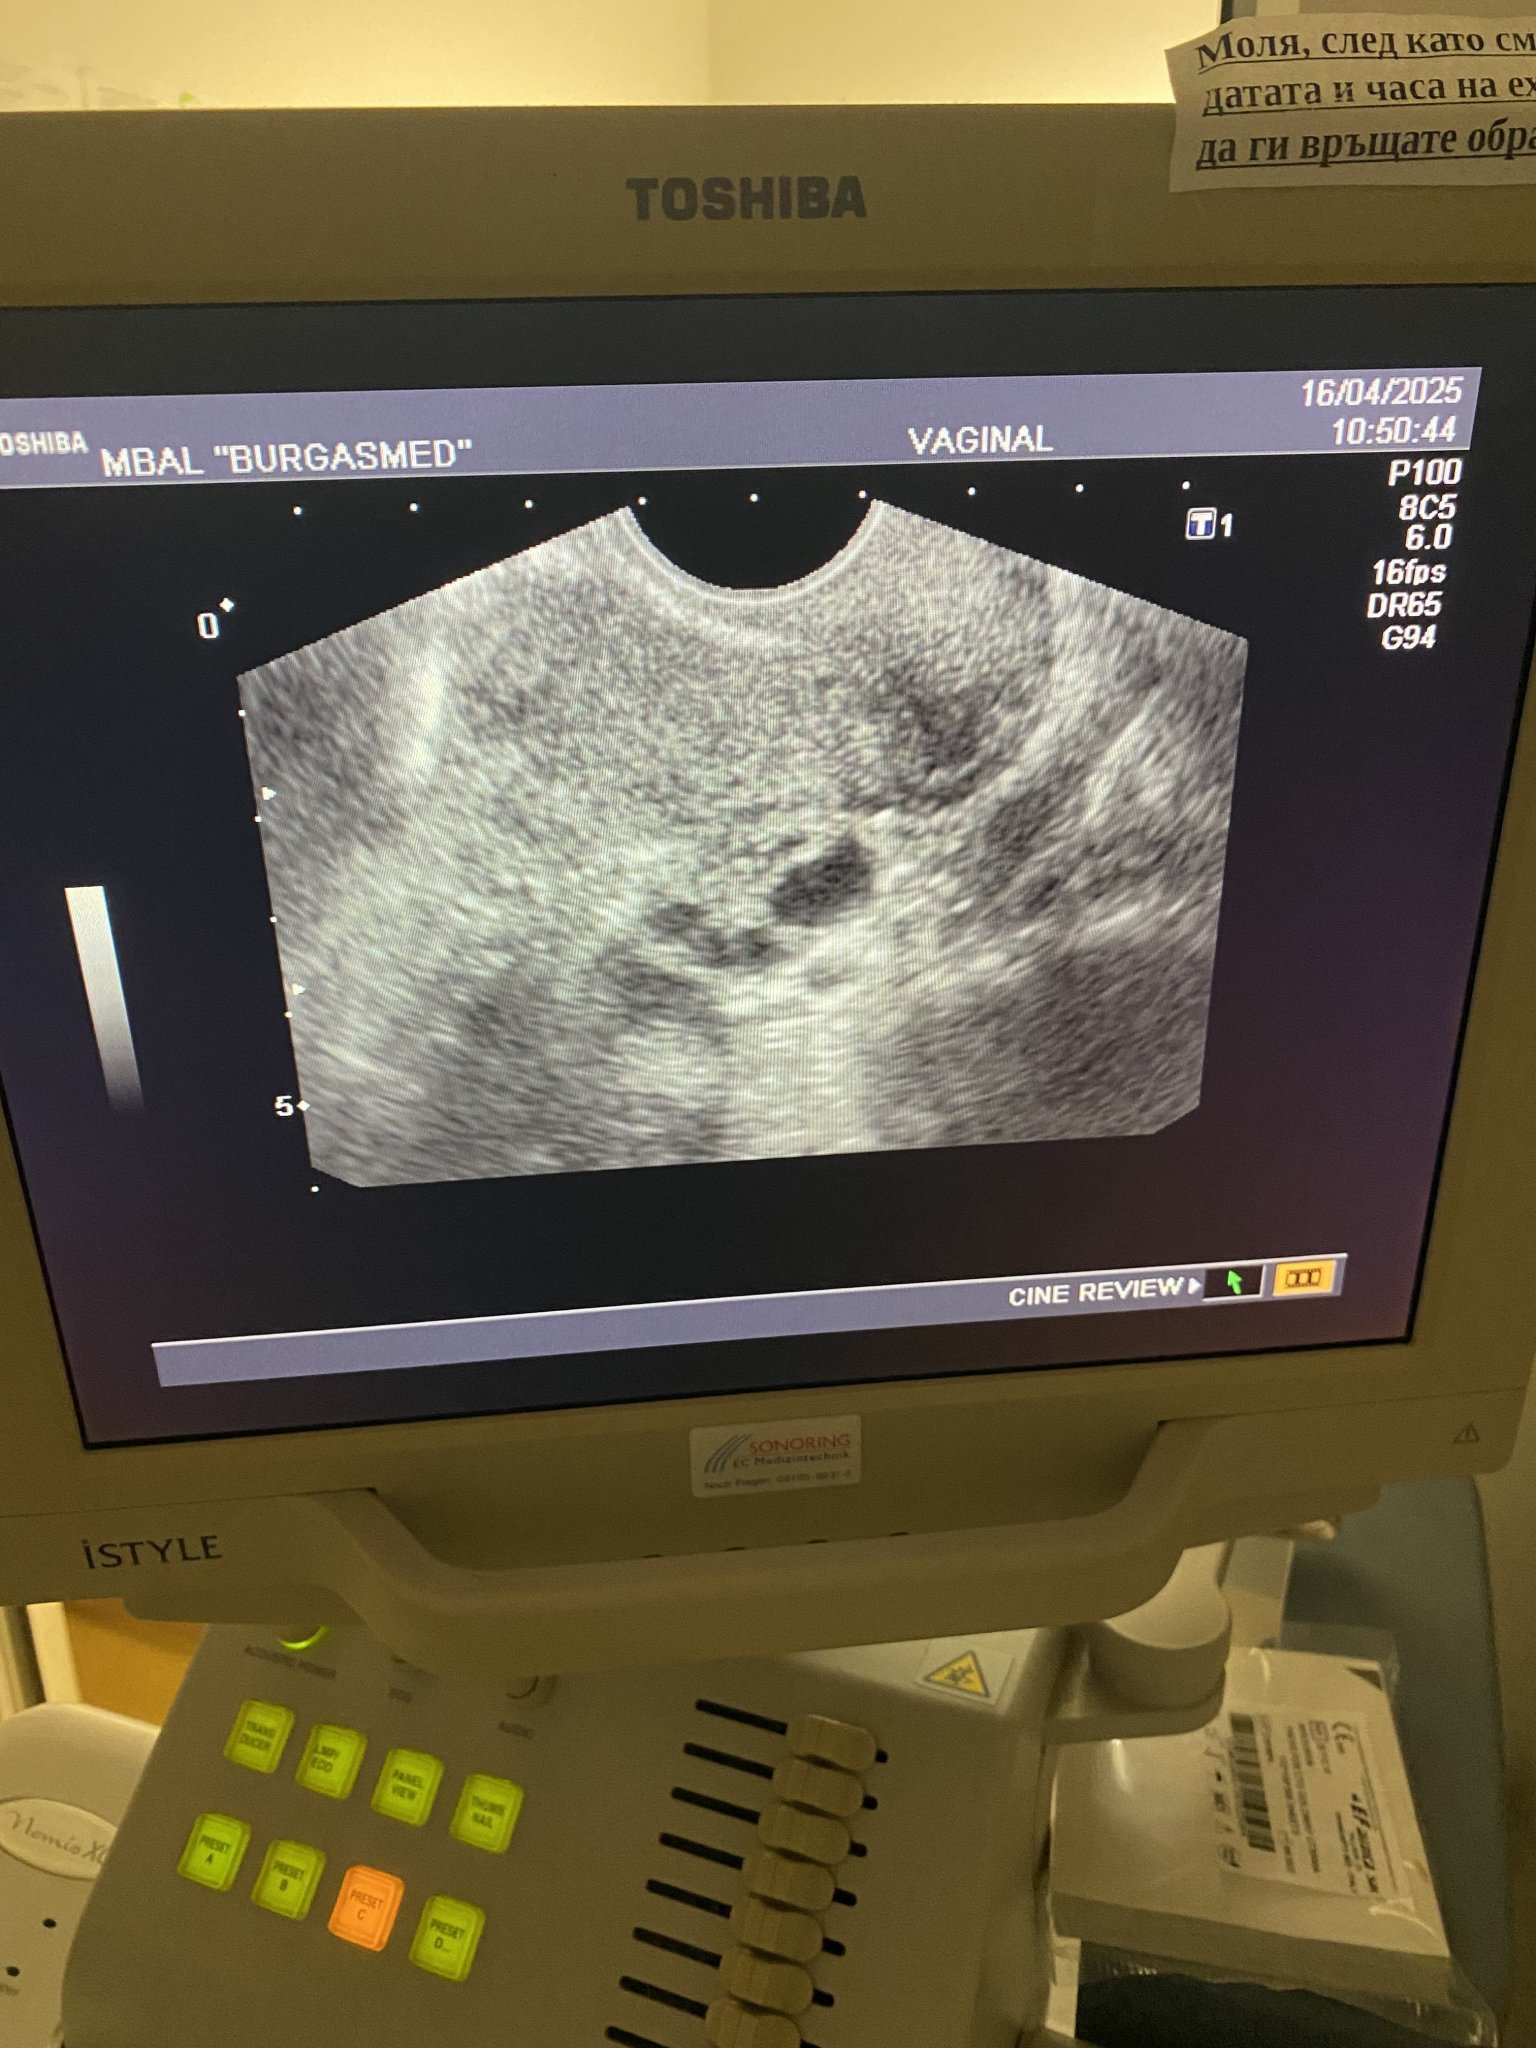

Здравейте! Може ли някой да ми каже дали всичко е наред? На първата снимка се видя, че бременността е маточна и каза, че всичко е наред, на втората снимка в 6 седмица все още не се чува пулс, каза, че плодния сак е пораснал и отговаря на седмиците си но каза нещо ембрионално не е пораснало. Не можах да разбера какво иска да каже с това, моля някой да ми помогне

Nadejda12,бременността се развива нормално. На долната ехографска снимка има напредък на развитието.